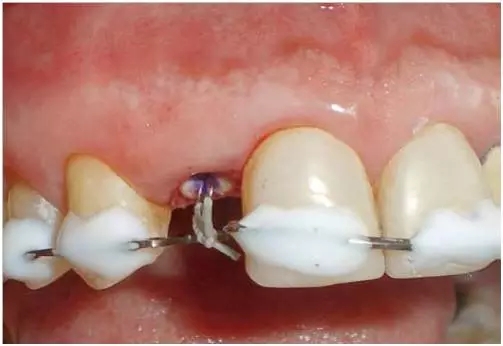

圖3:外傷9天后的臨床檢查:12牙牙冠在釉牙骨質(zhì)界水平處折斷。部分折斷面被牙齦覆蓋,可以看到中央有折斷的金屬根樁(鈦)。

圖8:在放置牙齦收縮線和橡皮障隔離12牙后的臨床檢查:采用聯(lián)孔技術(shù)放置橡皮障。用Permaflow purple 封閉橡皮障周圍并暫時固定于鄰牙。在口腔顯微鏡下用金剛砂鉆去除鈦根樁。